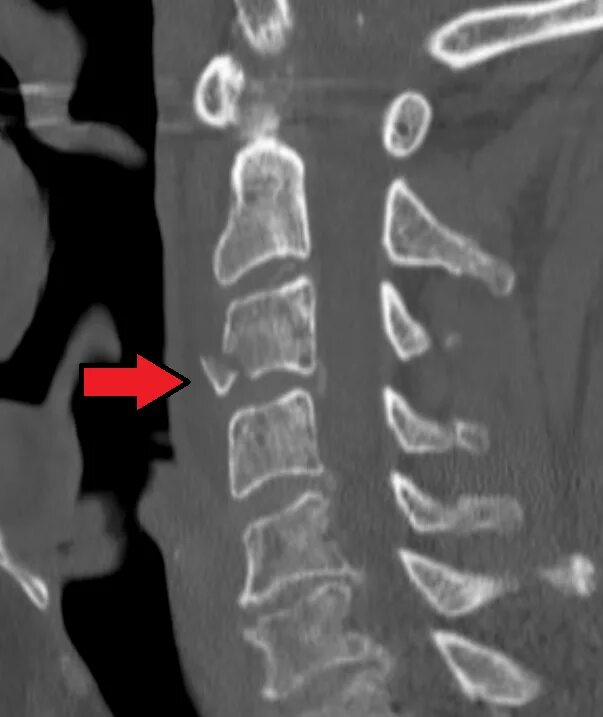

Перелом отростка l2